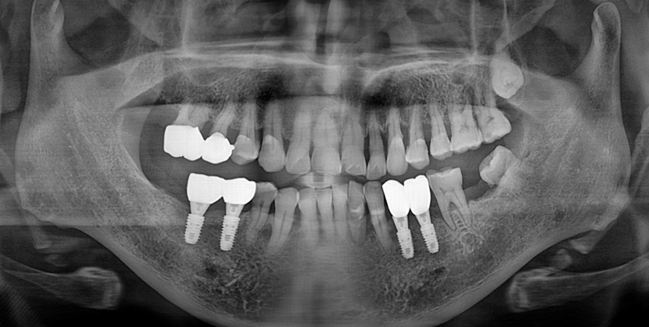

After

너무 늦지 않았다면 이런 어금니들도 크라운으로 씌워서 교합을 맞추고 구치부 지지를 회복할 수 있습니다.